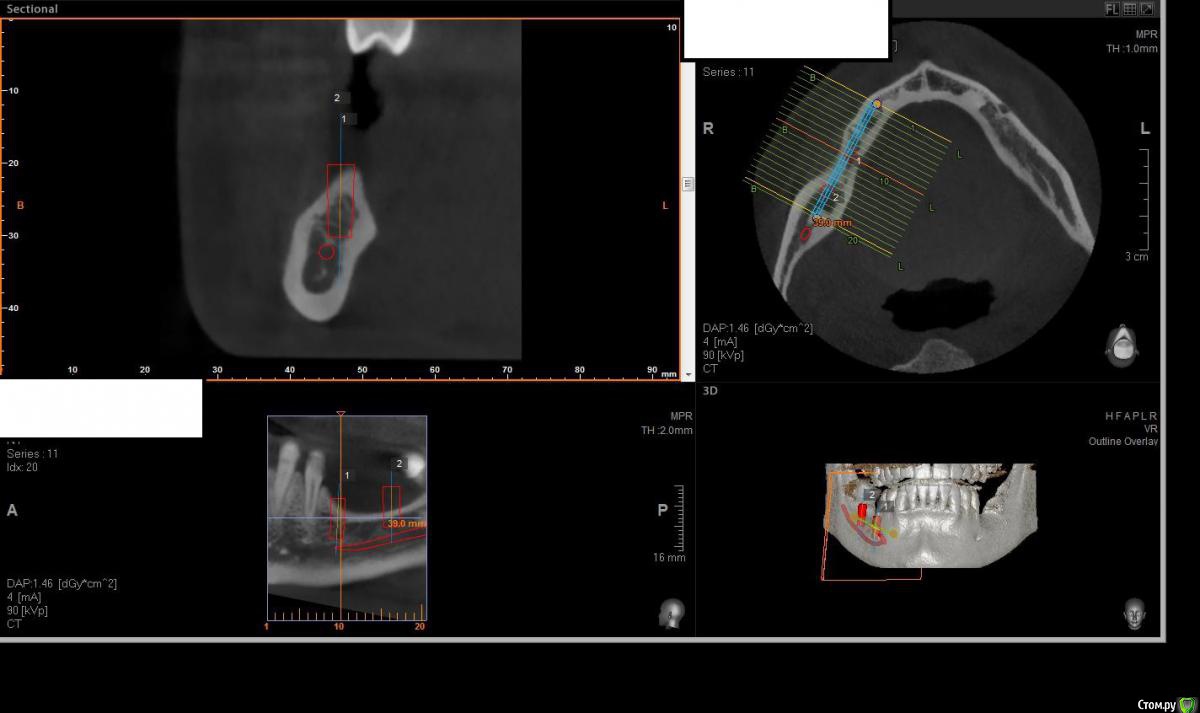

Павел7809 Опубликовано 21 ноября, 2017 Поделиться Опубликовано 21 ноября, 2017 Здравствуйте коллеги! Собственно ситуация на скринах. Для сосиджа как то экстремально большой объем. Блоки? Сетка?(ох как не хочется! последняя развалилась....) Крыша гаража? Из инструментария есть абсолютно все... Ссылка на комментарий

Павел7809 Опубликовано 21 ноября, 2017 Автор Поделиться Опубликовано 21 ноября, 2017 Коротышки с десной не рассматриваете? с удалением 8киинтересная идея...в принципе 2 астры туда влезают 4 на 6, боюсь просто эстетически получится некрасиво Ссылка на комментарий

Павел7809 Опубликовано 21 ноября, 2017 Автор Поделиться Опубликовано 21 ноября, 2017 Платформы имплантов будут на уровне апексов соседних зубов. Это будет эстетический ад. Ссылка на комментарий

Павел7809 Опубликовано 22 ноября, 2017 Автор Поделиться Опубликовано 22 ноября, 2017 (изменено) Да, но проблема в том , что на место 7 ки как бы и 6мм не влезает. Вообще мысль появилась поставить короткую 6 ку на месте 6 го зуба, удалить 8, поставить на его место имплант(там с местом проблемы нет, и сделать мостик) . Ну или сетка(ой как не хочется!) Мало того я посмотрел и понял что элементарно влезают восьмерки в обл 36 38 Изменено 22 ноября, 2017 пользователем Павел7809 1 Ссылка на комментарий

Павел7809 Опубликовано 25 ноября, 2017 Автор Поделиться Опубликовано 25 ноября, 2017 Пообщался с пациентом. Сошлись на коротышках 4 на 6 в область 7 ки, 9 на 4 в области 6 4ки. Да и по факту я посмотрел - коронки не будут такими уж огромными выглядеть. 1 Ссылка на комментарий